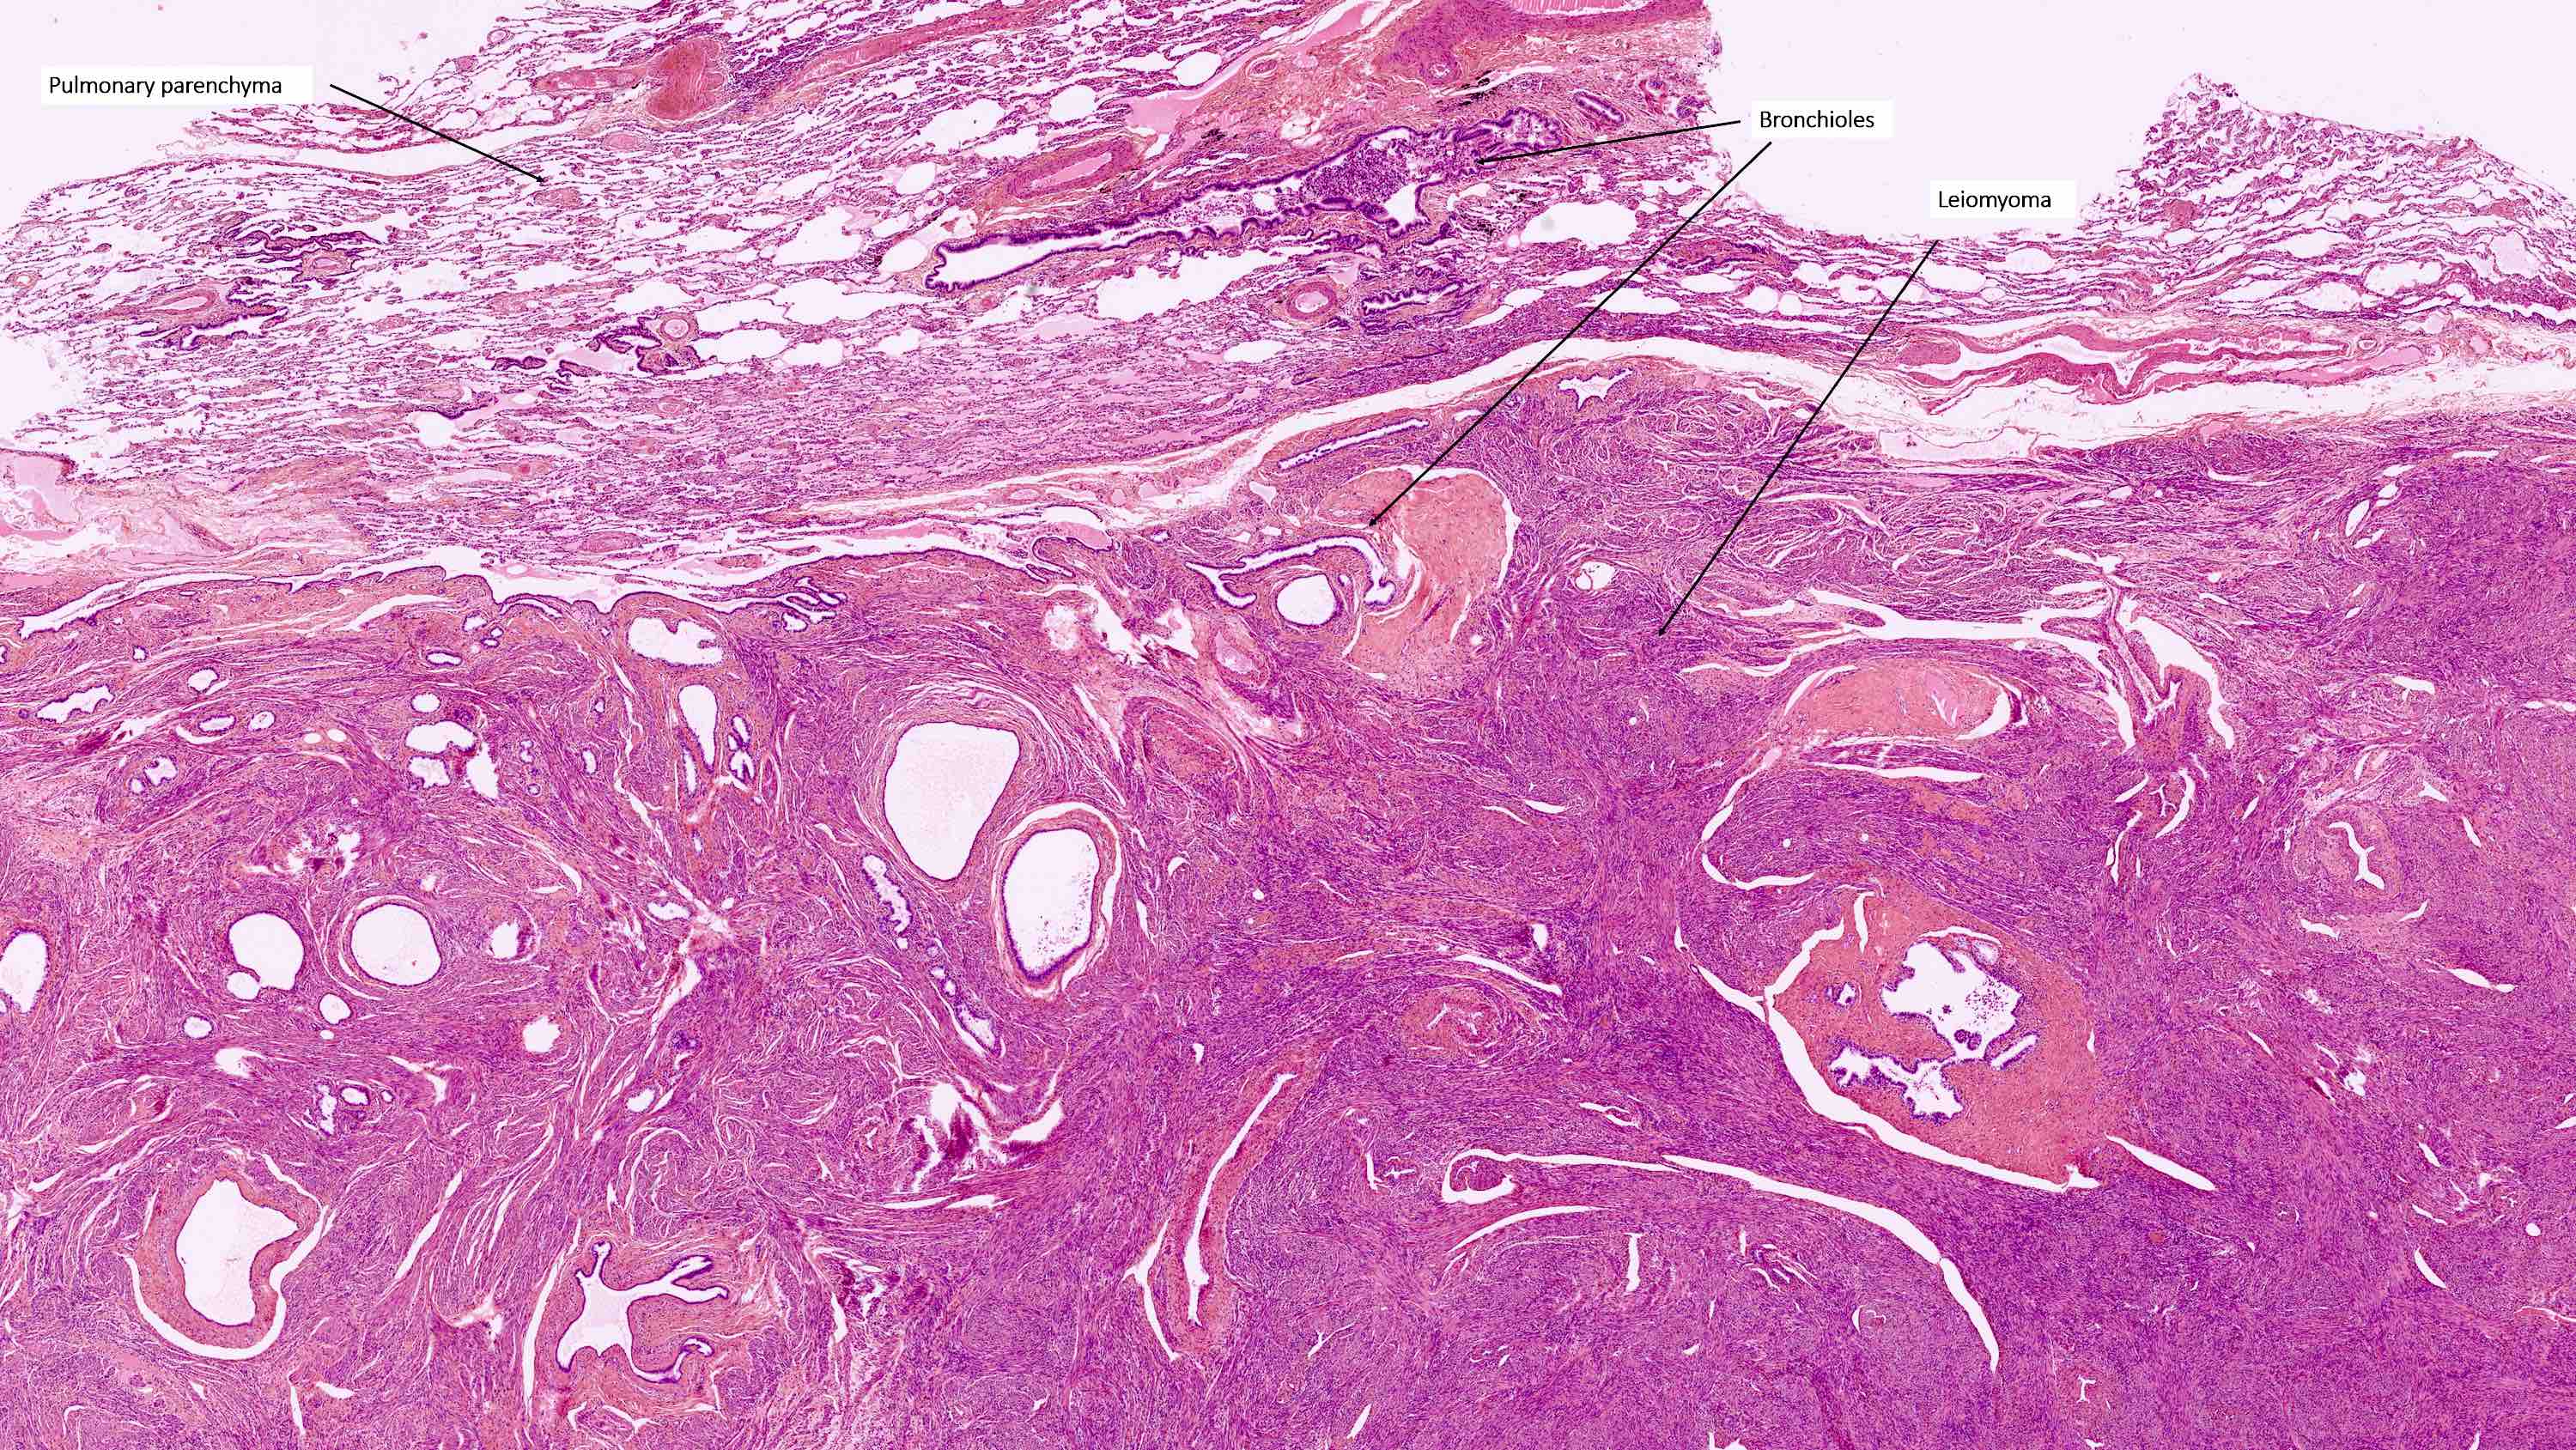

- Rare, benign appearing smooth muscle tumor in lung; may represent hematogenous spread of a uterine leiomyoma or a metastasis of a well differentiated leiomyosarcoma of low malignant potential (Mod Pathol 2006;19:130)

- Usually women 36 - 64 years, mean 44 years, with history of uterine leiomyoma

- Lung is most common site, sparing bronchus and pleura; also reported in lymph nodes, retroperitoneum, skin, bone, spine, skull base, heart

- Usually multiple nodules, up to a few centimeters in size

- Lesions tend to regress during pregnancy or after oophorectomy and stabilize or grow slowly in postmenopausal women

- Usually asymptomatic but may present with dyspnea, cough, hemoptysis, chest pain

- Chest Xray: diffuse, bilateral nodular opacities; rarely associated with miliary pattern, cavitary lesions, multiloculated cysts, interstitial lung disease (J Thorac Dis 2014;6:E92)

- Surveillance acceptable treatment for indolent, asymptomatic disease

Microscopic (histologic) description

- Conventional / usual leiomyoma (spindle):

- Well defined borders

- Normocellular

- Intersecting fascicles of monotonous spindle cells with indistinct borders, eosinophilic cytoplasm, cigar shaped nuclei (with tapered ends) and small nucleoli

- Atypia: absent or mild

- Mitoses: rare (in general < 5/10 high power fields)

- Blood vessels with thick walls

- With or without infarct type necrosis, hyalinization, calcification, cystic change

Microscopic (histologic) images

Contributed by Sabrina Croce, M.D., Ph.D., Kristina Doytcheva, M.D., Jennifer A. Bennett, M.D. (Case #508) and @Andrew_Fltv on Twitter